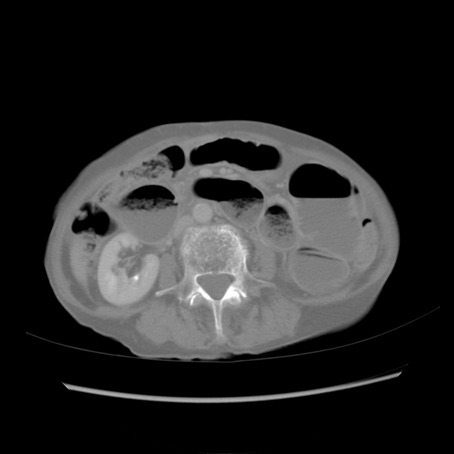

冠状断像

【症例】80歳代女性

【主訴】胸のつかえ感

【現病歴】約9時間前に食後から胸のつかえた感じあり、嘔吐あり、来院。

【既往歴】胃癌(全摘)、胆摘、虫垂炎

【身体所見】心窩部に圧痛あり、反跳痛なし。

【データ】WBC 5700、CRP 0.05